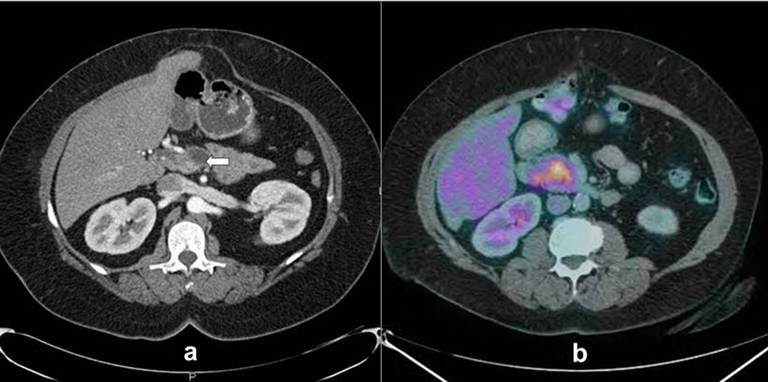

Fourteen months after the initial surgery, the patient was noted to have an elevated CA-19.9 level (75 U/mL: reference range: 0-37 U/mL), with main pancreatic duct dilation in the head of the pancreas on MRCP. Progressive main pancreatic duct dilation on MRCP and further elevation of CA-19.9 (133 U/mL) were noted 6 months later. Twenty-eight months after the original pancreas resection, the patient was referred to the University of Colorado for further management. A pancreas protocol CT scan showed diffuse heterogeneous enhancement of the head of the pancreas with marked main pancreatic duct dilation, measuring up to 1.7 cm in diameter, which was a new finding compared to previous studies (Figure 1a). Endoscopic ultrasound and endoscopic retrograde cholangiopancreatography examinations showed complete pancreas divisum; the ventral pancreatic duct in the head of the pancreas and pancreatic duct in the body of the pancreas were dilated markedly and diffusely. The entire opacified area contained a filling defect thought to be intraductal growth. The focal, large papillary growth within a mucin-filled dilated pancreas duct was biopsied, showing diffuse high grade dysplasia arising in the setting of suspected IPMN. A PET scan revealed a hypermetabolic pancreatic head mass with an SUV of 8 (Figure 1b). Review of outside slides from the distal pancreatectomy in 2007 by one of the co-authors (M.M.) revealed intraductal oncocytic papillary neoplasm with carcinoma in situ and microinvasion present at the original resection margin, with the subsequent surgical margin free of intraductal oncocytic papillary neoplasm.

Figure 1. a. CT scan with postsurgical clips status post distal pancreatectomy and splenectomy followed by pancreas re-resection at an outside hospital for a microscopically positive margin. The dilated pancreatic duct is marked with a white arrow. b. PET CT image shows diffuse uptake of contrast in the head of the pancreas. |